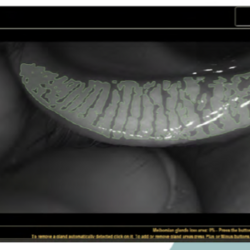

A Meibom mirigyek vizsgálata a szemhéj kifordítása után is nehéz feladat, általában a vizsgáló szubjektív megítélésre hagyatkozik. Miközben ma már meibográfiai eszközök segítségével pontos képet (szó szerint) kapunk a mirigyek telítettségéről, azaz a működésükről. Annyira személetes a fénykép, hogy páciensünk számára is könnyebben alátámaszthatjuk a kezelés szükségességét.